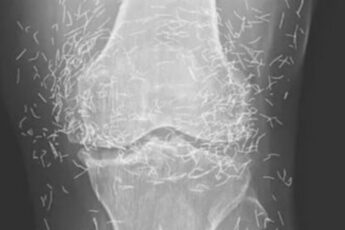

When a 65-year-old woman from South Korea went to the hospital for chronic knee pain, doctors expected